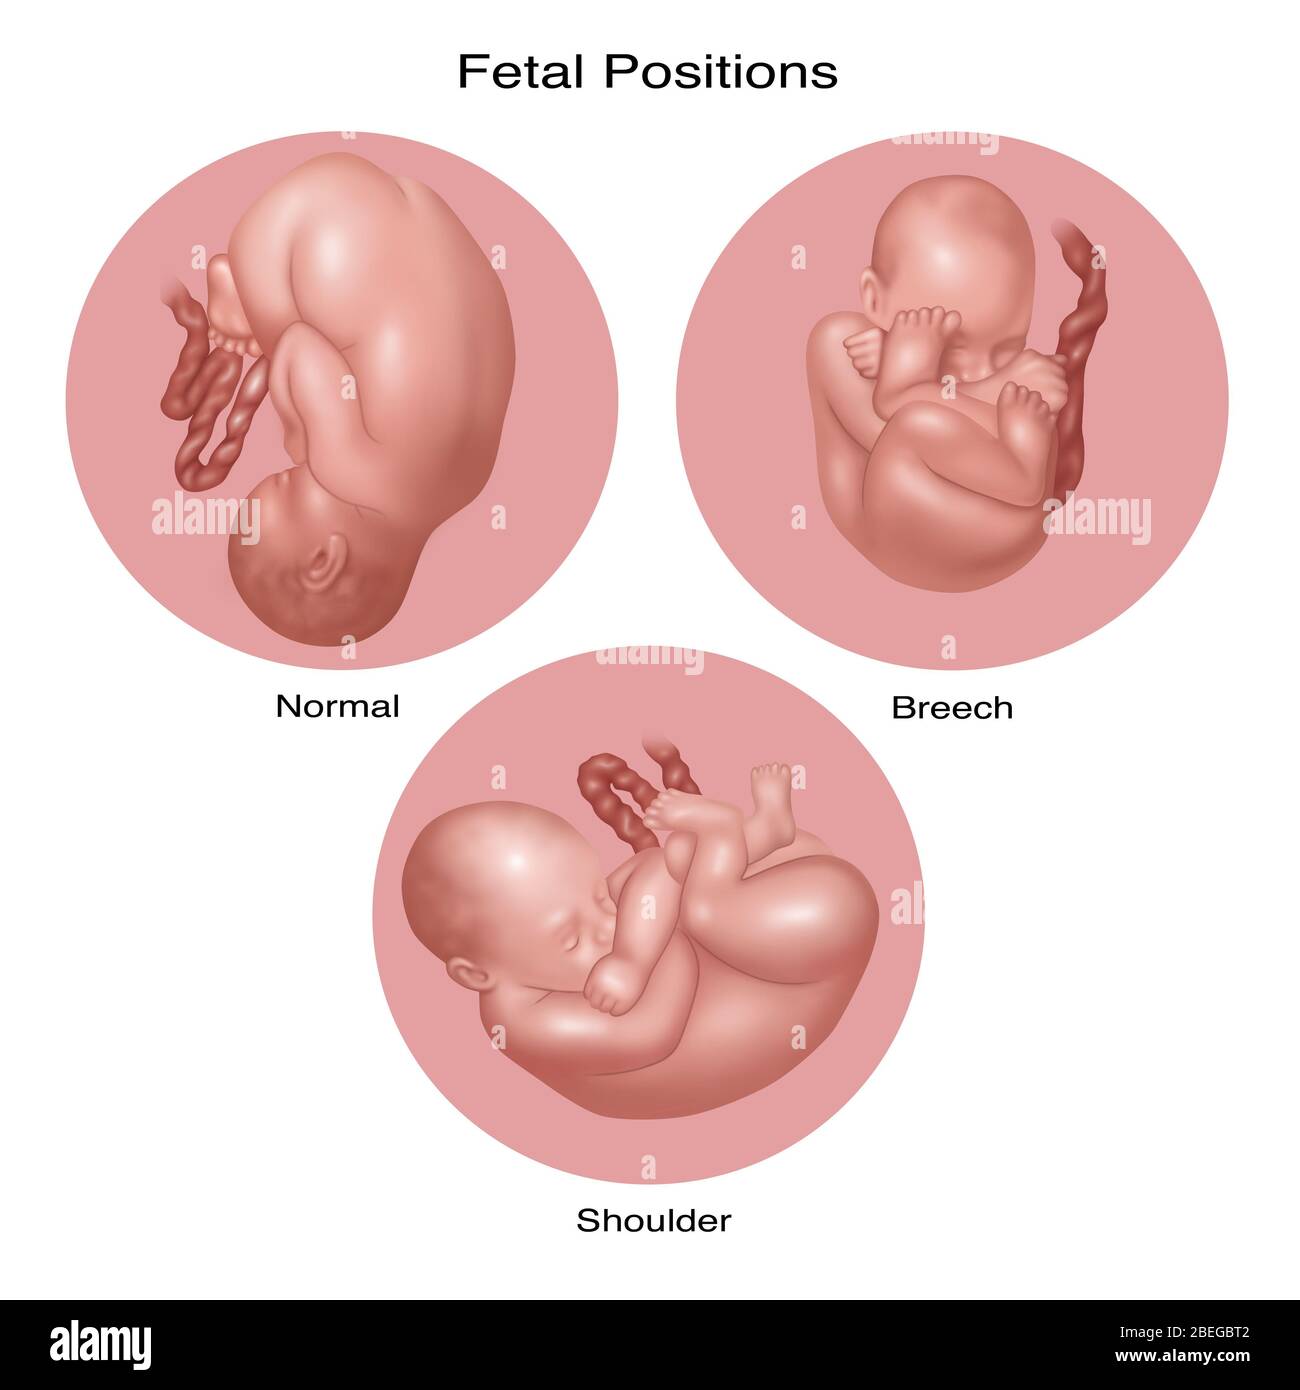

Fetus Positions in Uterus, Illustration Stock Photohttps://www.alamy.com/image-license-details/?v=1https://www.alamy.com/fetus-positions-in-uterus-illustration-image353173031.html

Fetus Positions in Uterus, Illustration Stock Photohttps://www.alamy.com/image-license-details/?v=1https://www.alamy.com/fetus-positions-in-uterus-illustration-image353173031.htmlRF2BEGBPF–Fetus Positions in Uterus, Illustration

Fetus Positions in Uterus, Illustration Stock Photohttps://www.alamy.com/image-license-details/?v=1https://www.alamy.com/fetus-positions-in-uterus-illustration-image353173074.html

Fetus Positions in Uterus, Illustration Stock Photohttps://www.alamy.com/image-license-details/?v=1https://www.alamy.com/fetus-positions-in-uterus-illustration-image353173074.htmlRF2BEGBT2–Fetus Positions in Uterus, Illustration